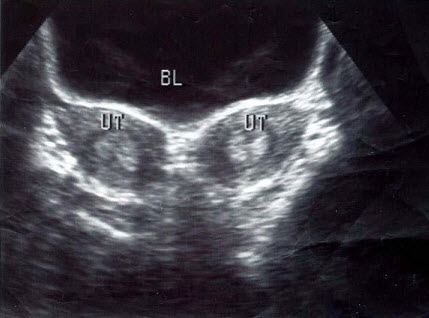

A.反射

B.衍射